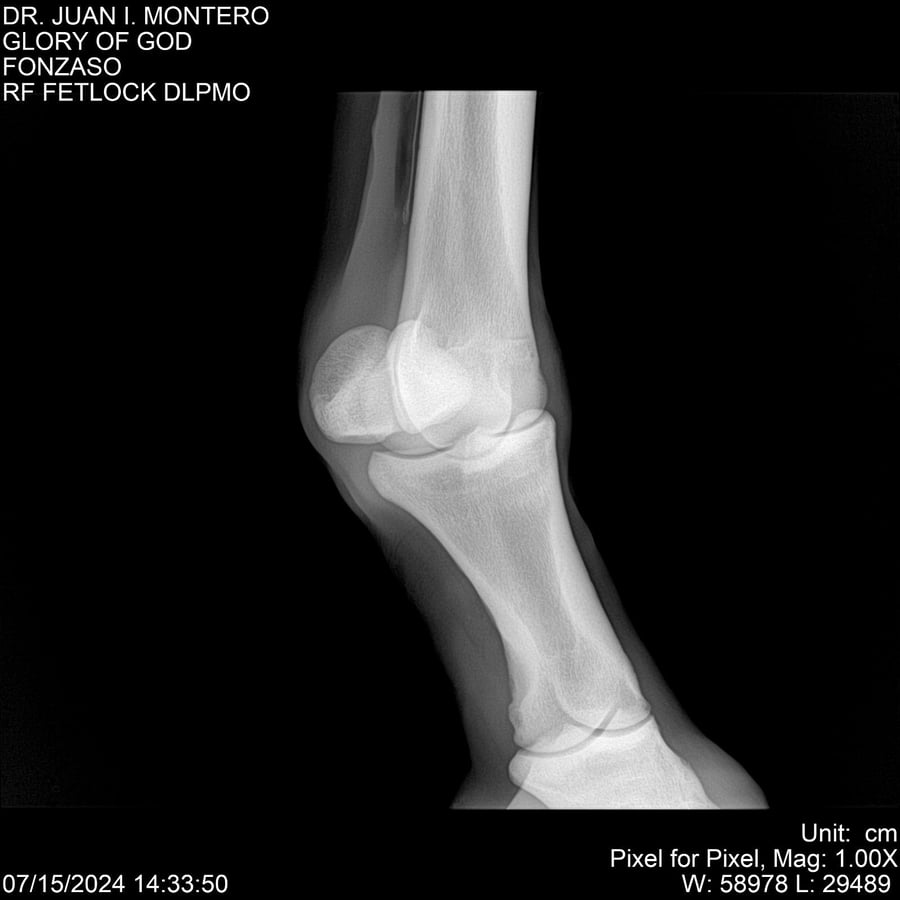

LOTE 10, GLORY OF GOD 🔥 🔥 🔥 Lote Anterior Volver al remate Lote Siguiente Ficha Contacto Montevideo - Ficha del Lote Identificador: #281389 Categoría: Yeguarizos Montevideo - 115 Visualizaciones ClicData Contacto Empresa: Abelenda N. R., Walter Hugo Nombre*: Teléfono* : E-mail* : Mensaje Enviar Registrese gratis Este contenido Exclusivo está disponible sólo para usuarios registrados Ingresar